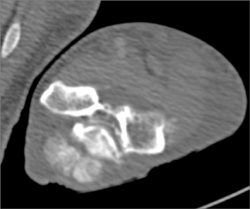

Ct Axillary Artery